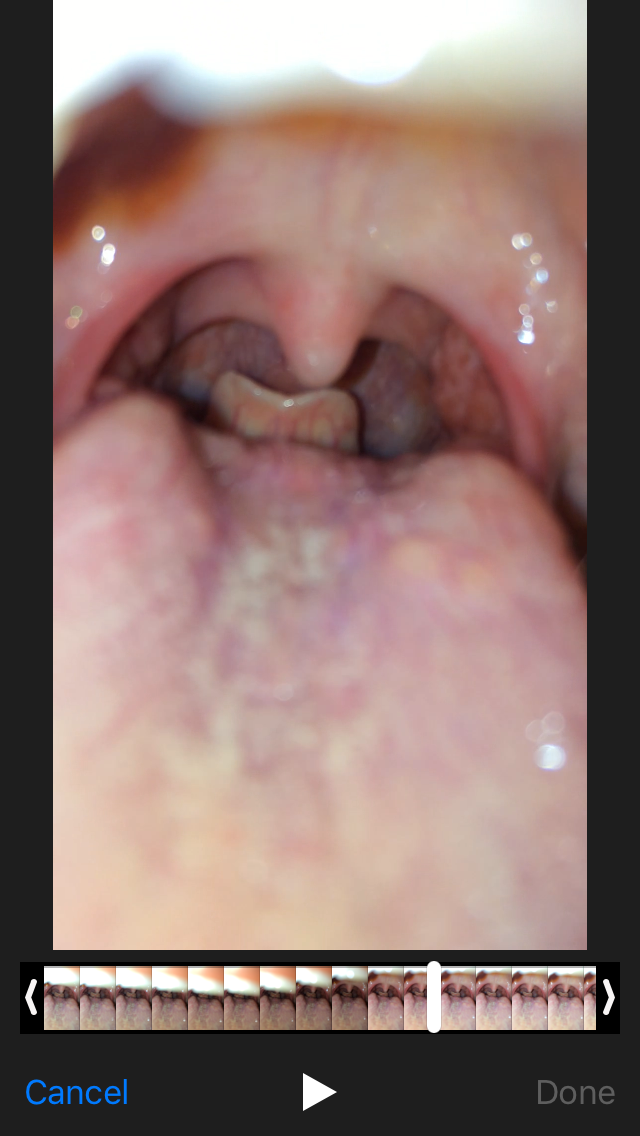

Asking for Self, Female, 21 years old, lahore

its in my mouth what is it

something is irritating in my throat since many days i feel like choking plz tell me what to do

Dear patient the picture is not this much clear. I suggest you to book an appointment with Marham for further evaluation. Thanks.